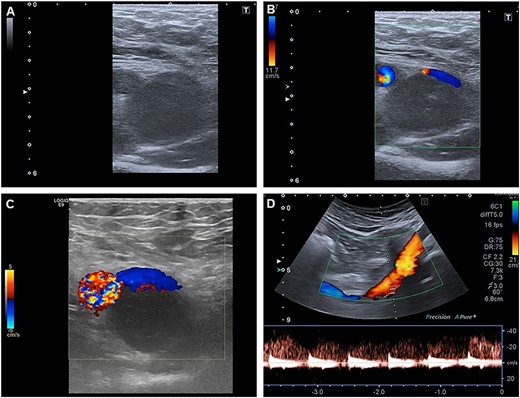

To clarify the entity of the lesion, MRI-Imaging and a fine needle biopsy were performed. In the MRI, the tumor had a slightly hyperintense signal in the T2-weighted images and a more hypointense signal compared to fat. In the T1-weighted images, the signal of the tumor was comparable to the muscular signal, and after application of contrast medium, a slight enhancement of the tumor was observed (Fig. 2). In the fine needle biopsy, proliferating cells were seen, but no conclusive histological diagnosis could be made.

T1-weighted MR-images of the right groin are presented pre- (A) and post-application of contrast medium (B). (A) A tumor with a diameter of 26 × 24 × 54 mm is seen dorsal to the common femoral vein and artery. In the left lower corner, a magnification of the area of interest is shown. CFV = common femoral vein; CFA = common femoral artery. (B) Addition of contrast displays the compression of the common femoral vein, but no flow impairment is seen. In the left lower corner, a magnification of the tumor is presented.